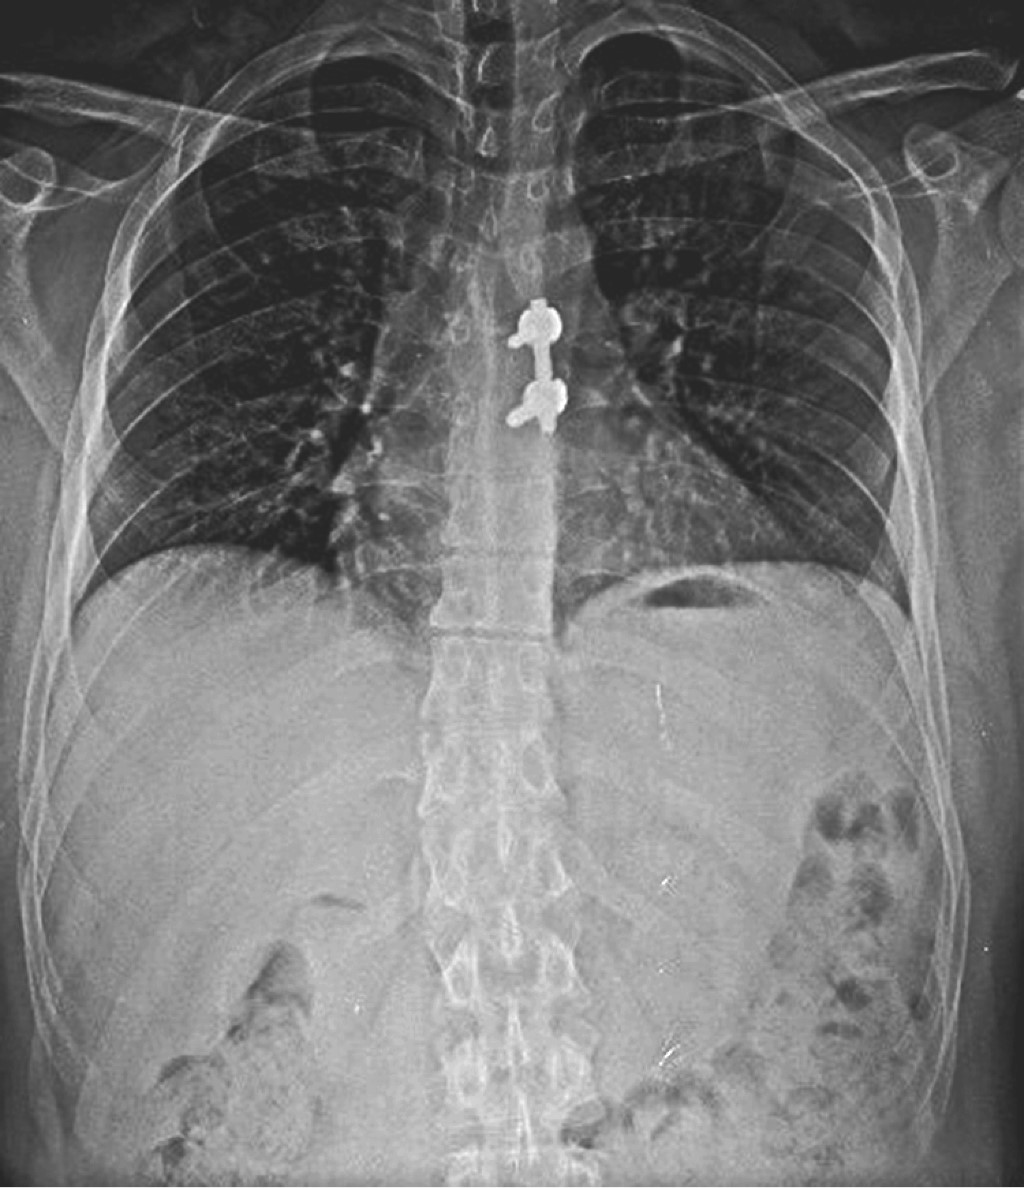

Se dio seguimiento al paciente en consulta externa cada dos semanas, el cual presentó recuperación del compromiso neurológico a las ocho semanas, logrando una marcha de características normales, con adecuada fuerza y sensibilidad en miembros pélvicos, sin datos de compromiso medular (Figuras 3 y 4).

Figura 3

Figura 4